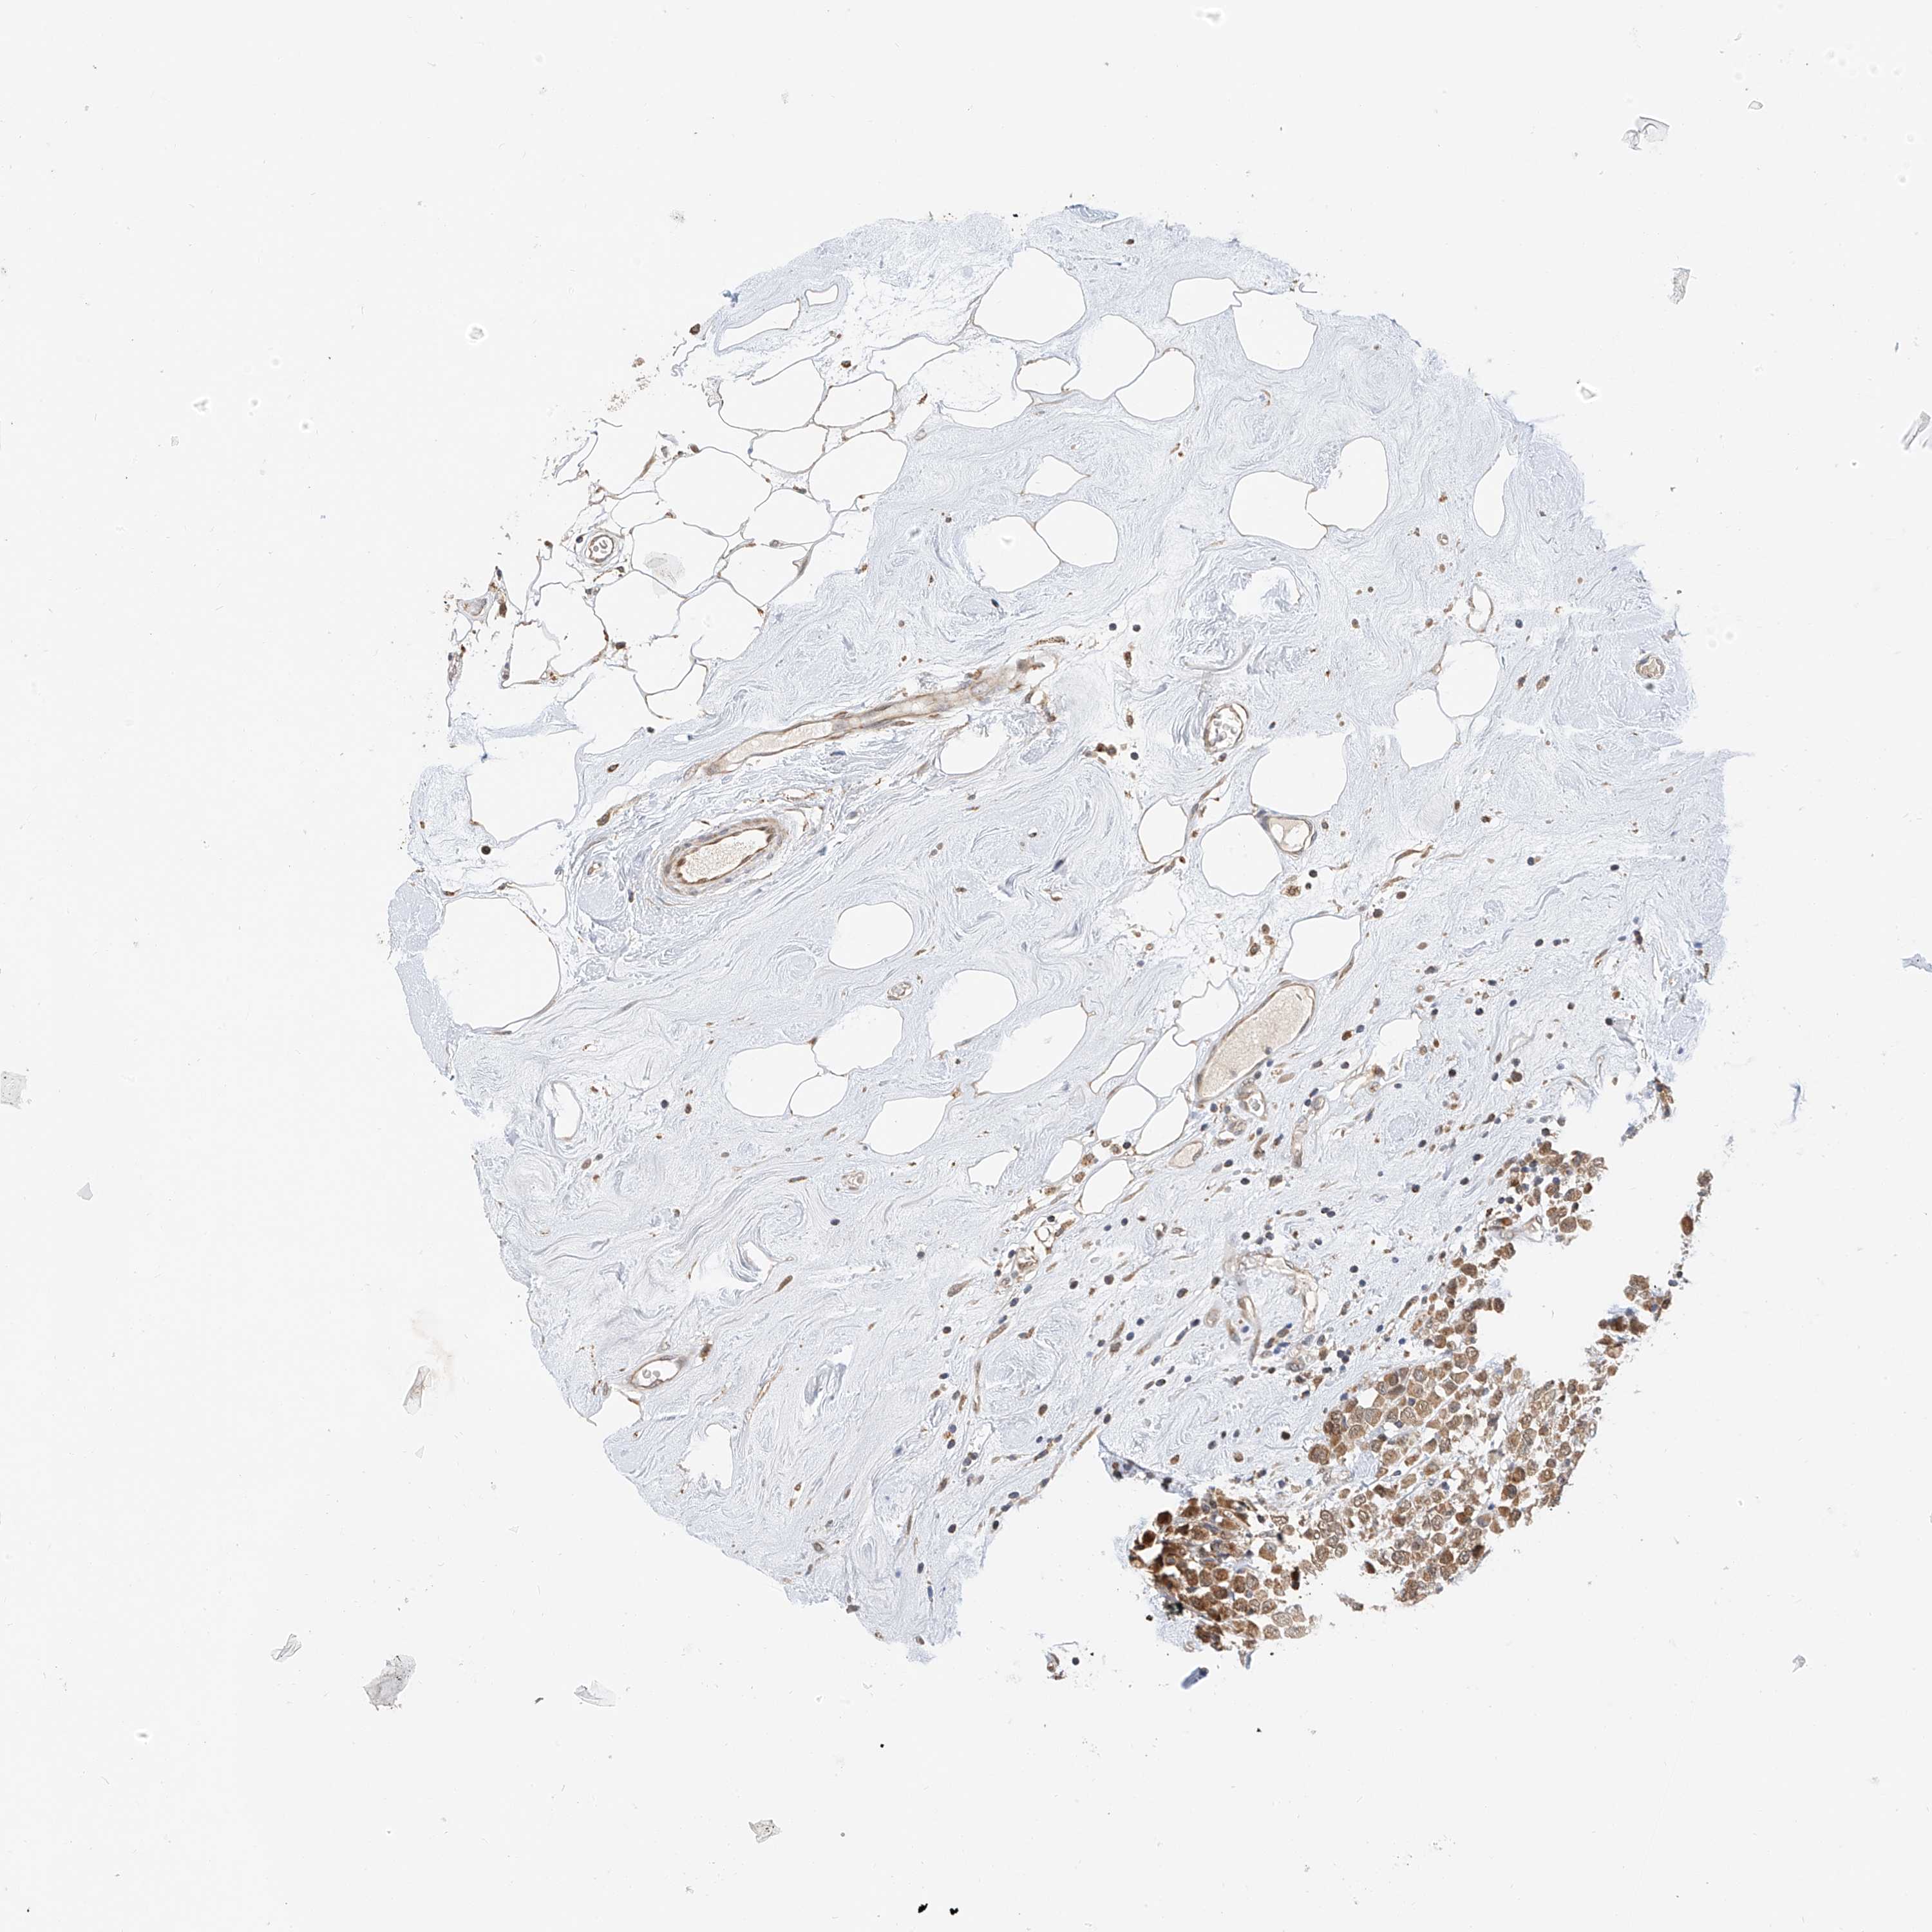

BRCA TCGA BRCA VALIDATION PROTEIN EXPRESSION

ANTIBODIES

AND

VALIDATION